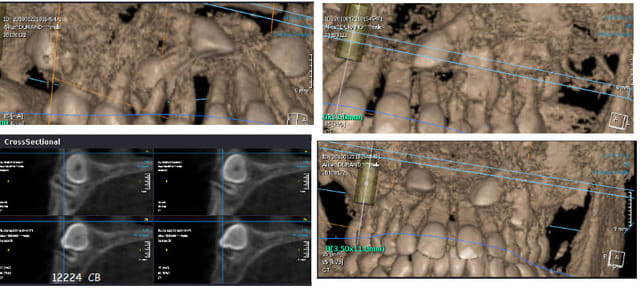

Voici quelques images de cone-beam.

C'est pas dans mes habitudes, mais là j'en ai quand même fait un pour voir les rapports 14-13.

ici, secteur 1, la 14 est la pièce maîtresse...coincée entre la racine de la 13 et de la 53, ainsi que sous la 54, si on veut la faire pivoter il lui faut de la place...=>extraction de 53/54

Pour 23 il faut exercer une force en vestibulaire, distal et occlusale. Faire une traction depuis un mulitbague ne permettrait pas d'avoir la composante vestibulaire et d'éloigner ainsi la couronne de 23 de la racine de 22. Une fois que la couronne de 23 n'a plus de risque que rentrer en contacte avec la racine de 22, l'on peut revenir a une traction plus classique " composante palatal, distal et occlusal.

Pour la 14 je dirais pareil vue le rapport avec la 13 je veux commencer par vestibuler la couronne de 13. Une fois la couronne vestibuler nous avons le champs libre pour tracter la 14.

Pour ce que je suis capable d’interpréter la 14 ne semble pas poser de problème particulier pour la mettre dans sa position normal.